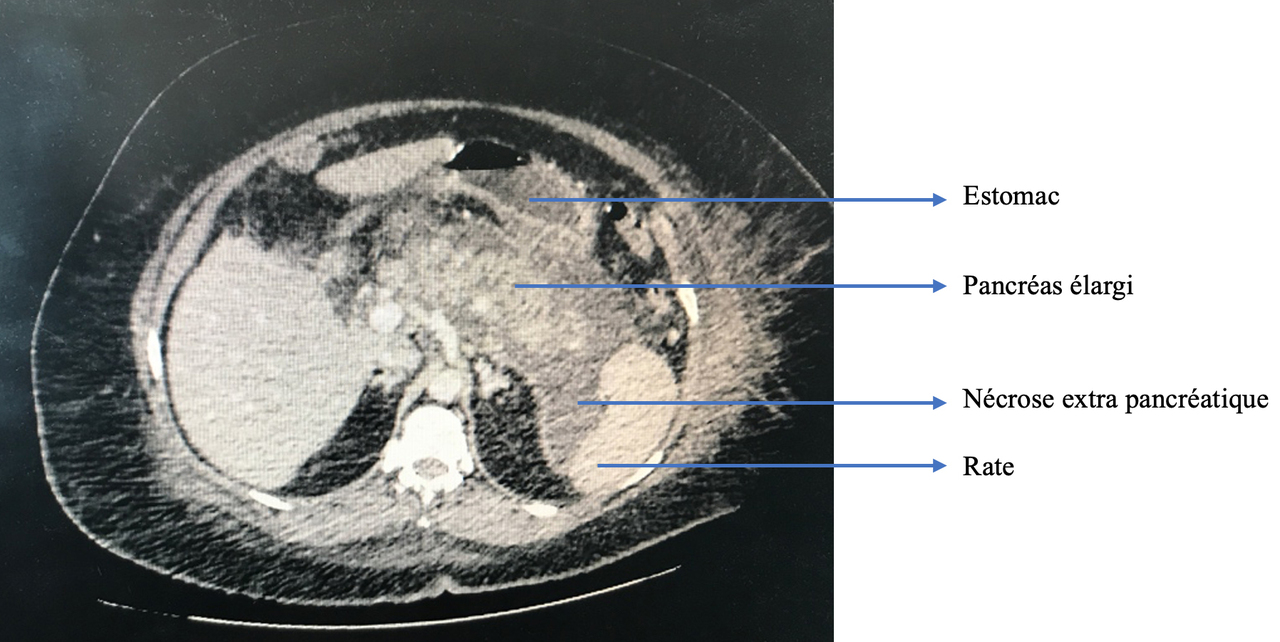

La douleur de la pancréatite est épigastrique irradiant dans le dos, majorée par la respiration profonde et la position antalgique est en chien de fusil.

– lithiasique : la plus fréquente ;

– alcoolique : elle survient le plus souvent sur un terrain de pancréatite alcoolique chronique mais peut aussi exister en dehors de l’alcoolisme chronique, sur alcoolisation aiguë massive (beaucoup plus rare).

Ces 2 causes représentent environ 80 % des pancréatiques aiguës.